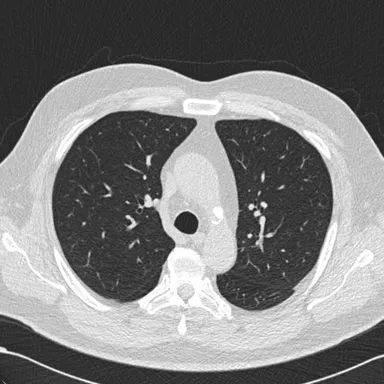

リリースTOP画像

・胸部CT肺血管透過処理システム/ClearRead CT-VS※2

胸部CT画像の肺血管を透過した画像を生成し、肺結節や異常陰影の視認性を向上させる。

・「ClearRead CT-VS」:胸部CT肺血管透過処理システム

- 肺組織の視認性を大きく向上

- 肺血管透過処理画像を生成

- 胸部CT画像上の病変の見落とし防止、気づきの促進